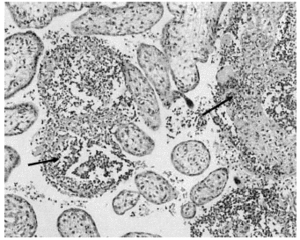

El informe anatomopatológico del feto objetivó la presencia de microabscesos viscerales por infección por Listeria (fig.1). En la placenta se apreciaron también microabscesos inter-intravellositarios (fig. 2).

Figura 1. Microabscesos por infección de L. monocytogenes en la glándula suprarrenal. Hematoxilina-eosina. 10X.